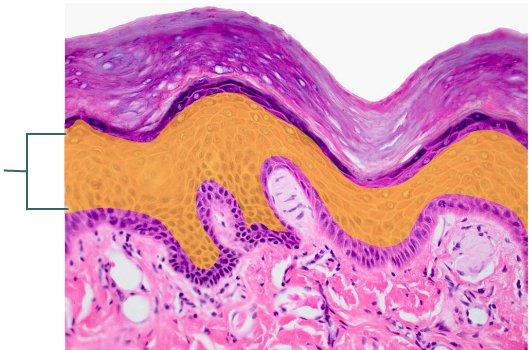

Which type of tissue is the highlighted region composed of?

stratum corneum

stratified squamous epithelium, keratinized

stratum spinosum

dermis

stratified squamous epithelium, keratinized

Which structure is highlighted?

stratified squamous epithelium, keratinized

stratified squamous epithelium, non-keratinized

stratified cuboidal epithelium

stratified columnar epithelium

stratified squamous epithelium, keratinized

Which layer of the skin is highlighted?

papillary layer of dermis

reticular layer of dermis

hypodermis

epidermis

papillary layer of dermis

Which region of the skin is highlighted?

hypodermis

reticular layer of dermis

epidermis

papillary layer of dermis

Which layer is highlighted?

papillary layer of dermis

hypodermis

reticular layer of dermis

epidermis

hypodermis